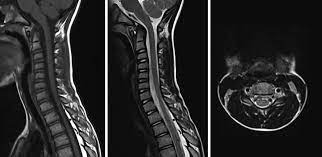

অ্যাকিউট ফ্ল্যাকসিড মাইলাইটিস  বা এএফএম হলো একটি স্নায়বিক রোগ, যার ফলে, শরীর পক্ষাঘাতগ্রস্ত হয়ে পড়ে। ২০১৪ সাল থেকে প্রতি দুবছরে একবার করে অ্যাকিউট ফ্ল্যাকসিড মাইলাইটিস হানা দিয়েছে মার্কিন যুক্তরাষ্ট্রে।

এখনও পর্যন্ত এই রোগের কোনও প্রতিকার বা চিকিৎসা নেই। তাই রোগ নির্ণয় দ্রুত হলে, উপসর্গগুলির চিকিৎসা শুরু করা সম্ভব হবে। ফলে, থেরাপির মাধ্যমে আক্রান্তদের পক্ষাঘাতগ্রস্ত হাত ও পা পুনরায় সচল করতে তা সাহায্য করবে।